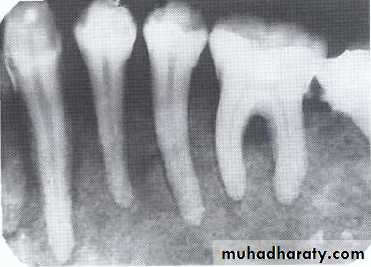

Dentigerous CystIt forms around the crown of an unerupted or supernumerary tooth at CEJ.

Some dentigerous cysts are eccentric, developing from the lateral aspect of the follicle so that they occupy an area beside the crown instead of above the crown.

It displace and resorb adjacent teeth.

It commonly displaces the associated tooth

in an apical direction.